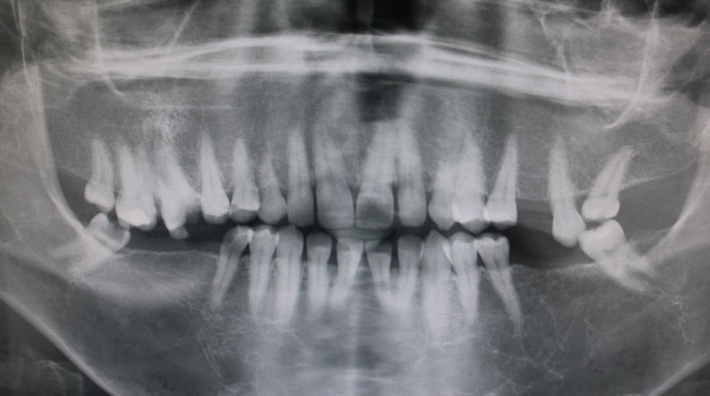

The patient underwent radiological examination. The panoramic views revealed the enlargement of marrow spaces with widened trabeculae in both the maxilla and mandible (Figure 2). The soft tissue drapes had normal color and contours. The only abnormal finding in soft tissue examination was macroglossia (Figure 4).

Figure 3.Panoramic view of the enlargement of marrow spaces with widened trabeculae.

β-thalassemia is due to the diversity of genetic defects resulting in diverse hematologic and clinical features such as anemia. There are several different genotypes that may present similar clinical manifestations. Accordingly, Margot reported such manifestations as generalized rarefaction of the alveolar bone, thinning of cortical bone, “chicken-wire” appearance of the widened bone marrow spaces, and large trabeculae in radiographic examinations.23 We also observed the enlargement of marrow spaces with widened trabeculae in both the maxilla and mandible. Other dental anomalies, which may occur along with tooth transposition, include agenesis or malformation of lateral incisors and the retention of deciduous teeth.14